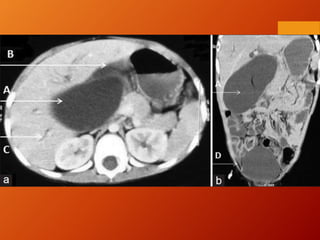

Contrast CT- Peritoneography

(traditional method/Old method)

 provides the highest resolution in the

delineation of anatomic details and the

demonstration of extra peritoneal fluid.

contrast CT peritoneography was also used to

evaluate the functional surface area of the

peritoneum with stereological methods

Drawback: CT peritoneography time-

consuming